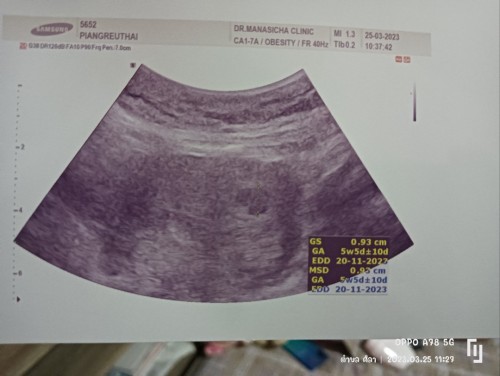

ท้อง2แต่ก็ยังแอบกลัววันนี้เจอแค่ถุงตั้งครรภ์ แม่ๆเจอตัวน้องตอนกี่วีคบ้างค่ะ

เจอตัวน้องตอน8weekค่ะ ซาสด์ครั้งแรกตอน5week เจอแค่ถุง